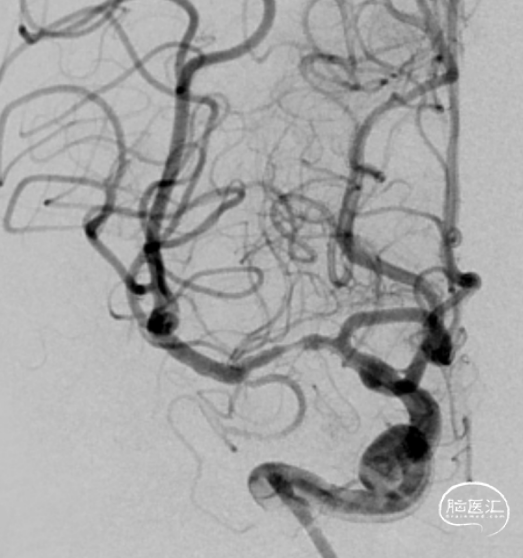

术前造影:

造影显示RICA:C1段起始部闭塞,残端呈锥形,TICI分级0级;RMCA未显影,远端由RACA经皮层支少量代偿,ASITN分级1-2级。